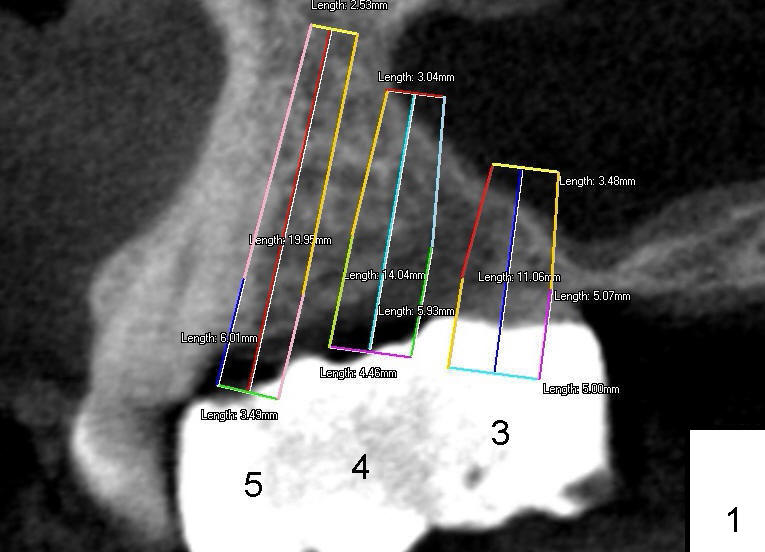

It appears that sinus graft is necessary for #3-5 implant placement (Fig.1). Mr. Wu says "Do whatever you think appropriate." But the framework partial denture is suddenly broken at the major connector. He cannot eat well. We do not have time to do sinus graft! Short implant is planned to be placed at the site of #3 (5x11 mm, Fig.1). After initial bone expansion until RT 2 mm (as mentioned above), two-mm pilot drills are inserted at the sites of #3 and 5 (Fig.2). The sinus floor is perforated at #3. The osteotomy for #3 is then moved mesially ~ 2 mm using osteotomes (RT 2-4mm). While bone expansion (osteotomes and taps) is being used to create osteotomy for #3, tapered drills for #5. Fig.3 shows 5x11 mm tap and 3.5x20 mm drill in place. Finally 6x11 mm and 4x20 mm implants are placed with >60 Ncm (Fig.4). The patient is also doing great nearly two weeks postop. A third implant is planned to be placed at the site of #5 1-3 months later.